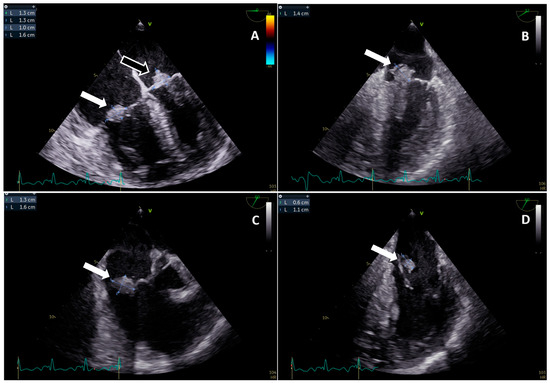

An Unusual Case of a Double Tricuspid and Mitral Valves Infective Endocarditis Complicated by Multiple Septic Embolisms Secondary to an Atrial Septal Defect: A Case Report and Review of Literature

| Our clinical case | 68 | Male | Interatrial defect * | Staphylococcus aureus MR | Native TV and MV | Yes | Lungs | Brain, spleen, vertebral bones | Yes | Alive |